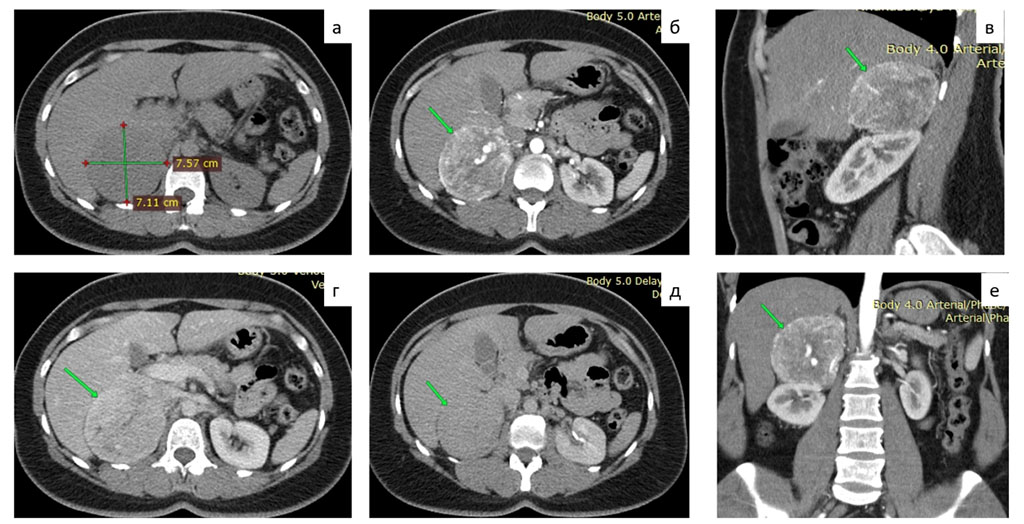

CT scan of the thoracic and abdominal organs with contrast: thoracic organs without pathology. In the right adrenal gland, a neoplasm of 75 mm, with even clear contours, tightly adjacent to the lower surface of the right lobe of the liver, to the anterior surface of the upper part of the right kidney, to the inferior vena cava, with a density of +25HU, in the arterial phase up to +116HU, in the venous phase up to + 105HU, 10 minutes after administration of imaging agent +60 HU. Large vessels are seen in the structure of the neoplasm. Fig. 1.

Figure 1. MSCT of the abdomen with contrast: a - native phase, b, c, f - arterial phase, d - venous phase, e - delayed phase.